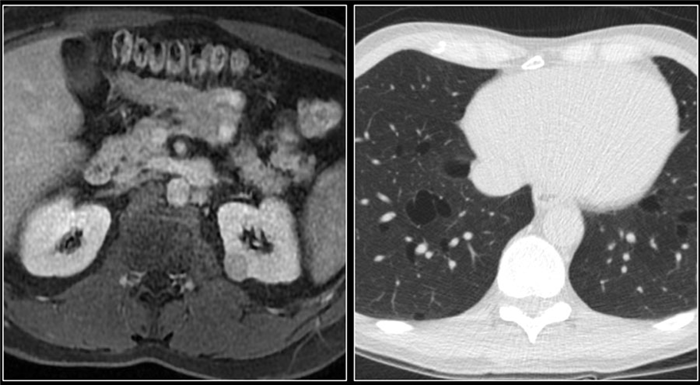

При визуализации картина при пиелонефрите или абсцессе почки схожа с картиной при опухоли, поэтому результаты анамнеза, осмотра и других клинических данных помогают радиологу в постановке правильного диагноза. В представленном случае визуализируются гиподенсные образования в обоих почках. Если диагноз базировать только, исходя из данных изображения, то напрашивается следующий дифференциальный ряд: пиелонефрит, лимфома или метастаз.

Данный пациент поступил с жалобами на боль в боку и с анамнезом воспалительного поражения мочевыводящих путей, также у пациента отрицательный онкологический анамнез, поэтому диагноз — пиелонефрит.

На КТ спустя 4 месяца визуализируются нормальные почки. На первом изображении патологическая картина обусловлена мультифокальным пиелонефритом.

Абсцесс почки является осложнением острого пиелонефрита. Обычно у данных пациентов лихорадка, боль и в анамнезе инфекция мочевыводящих путей.

На КТ абсцесс визуализируется, как неспецифическое однородное гиподенсное образование или комплекс кистозных образований.

Почечный абсцесс также может визализироваться, как образование с утолщённой стенкой неравномерно контрастирующееся с прорастанием в околопочечную клетчатку.

У пациентов с атипичной клинической картиной и кистозно-комплексного образование с прорастанием в околопочечную клетчатку в дифференциальный ряд следует включить почечно-клеточный рак.

Этот пациент типичный поступил с болью в правом боку и изменениями в лабораторных данных, характерные для инфекции мочевыводящих путей.

На ультразвуковом изображении визуализируется гипоэхогенный очаг с гиперэхогенным включением, что соответствует на жидкостное включение.

Диагноз — абсцесс.

Ксантогранулематозный пиелонефрит.

Ксантогранулематозный пиелонефрит (КП) — это агрессивная форма интерстициального нефрита, включающая гнойно-деструктивный и пролиферативный процессы в почке с образованием гранулематозной ткани. Часто патология ассоциирована с мочекаменной болезнью, что приводит к дополнительной дилатации чашки. В таких ситуациях почка чаще диффузно увеличена, реже сегментарно.

Увеличение почек присутствует во всех случаях ксантогранулематозного пиелонефрита и при макроскопическом исследовании выявляются включения жира. Ниже представлен ещё один случай ксантогранулематозного пиелонефрита. У пациента деструкция правой почки, множественные конкременты и пролиферация фиброзной и жировой ткани. Данная КТ очень напоминает липосаркому.